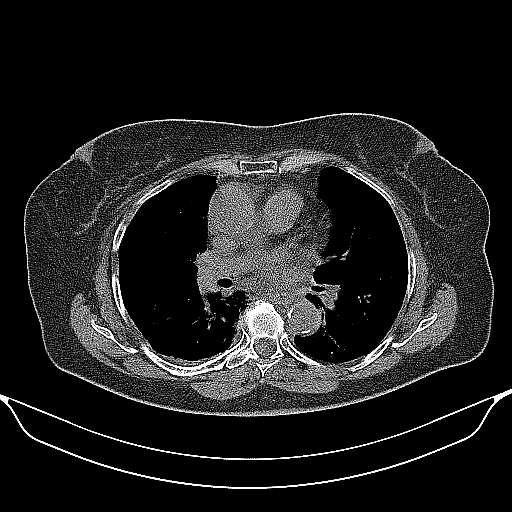

Reconstructed NATIVE CT scan (cycle consistency)

Full window (WL 1023.5, WW 4095 β†’ Low βˆ’1024, High +3071)

Actual HU range: [-1024.0, 1512.0]